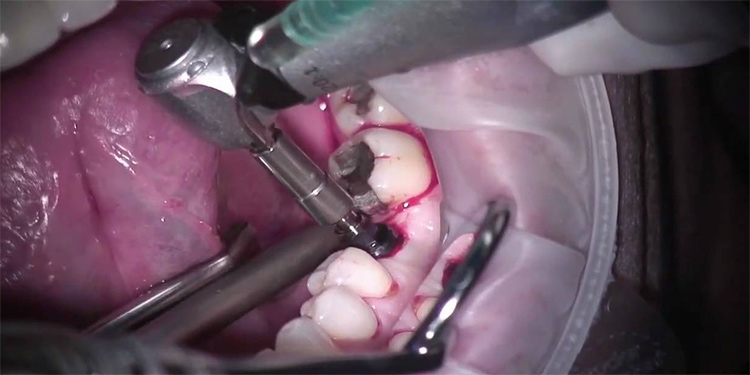

Quy trình cấy ghép implant trải qua nhiều bước khác nhau. Bước quan trọng nhất là thời gian cấy trụ implant vào xương hàm. Đây có thể coi là một cuộc tiểu phẫu. Ở bước này đòi hỏi bác sĩ phải thực hiện thao tác chính xác để tích hợp implant và xương đúng vị trí tối ưu. Cấy ghép phải được thực hiện trong phòng vô trùng để ngăn ngừa mọi nguy cơ nhiễm trùng có thể xảy ra.

Sau gây tê, bác sĩ sẽ rạch một đường ở rìa ổ răng, sau đó tạo lỗ và đặt trụ implant, thời gian phẫu thuật chung là 20-30 phút.